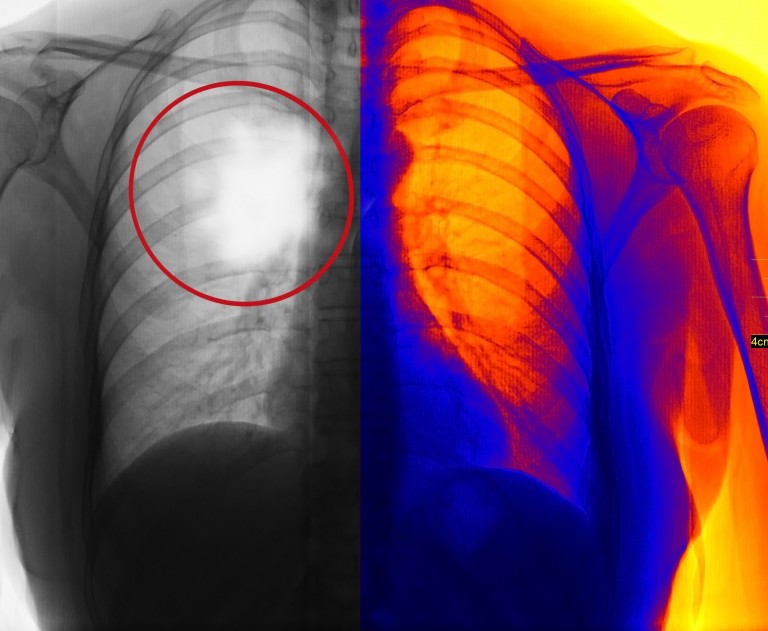

Due to the way in which asbestos enters the body, the most common

form of mesothelioma is found on the pleural membrane; the lining of the

lungs. It is rarer than lung cancer, with about 2,500 new cases